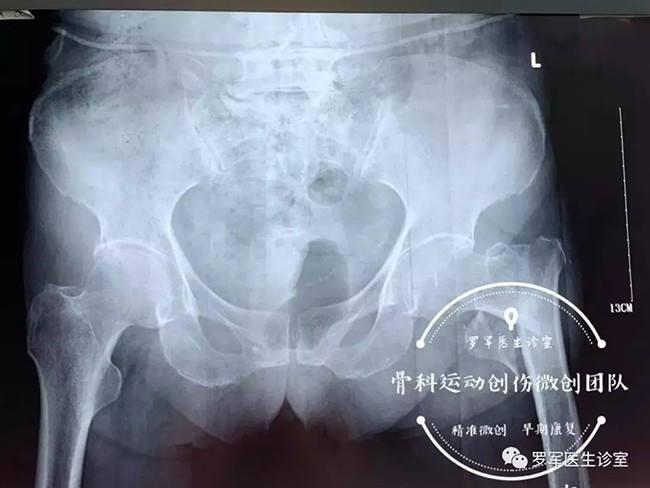

今年86歲高齡的丁奶奶就是其中的一位患者,前不久,丁奶奶走路時(shí)不幸摔倒,造成左側(cè)股骨粗隆間粉碎性骨折,被送到廣安醫(yī)院關(guān)節(jié)科救治。

經(jīng)過(guò)入院檢查發(fā)現(xiàn)丁奶奶合并有高血壓,糖尿病,動(dòng)脈粥樣硬化、低蛋白血癥及嚴(yán)重的骨質(zhì)疏松,“無(wú)論采取保守治療還是手術(shù)治療,風(fēng)險(xiǎn)都很大。但對(duì)于高齡老人的骨折,放棄手術(shù)就等于放棄生的希望。”羅軍主任介紹,髖部骨折對(duì)高齡、身患各種慢性病的老年人來(lái)說(shuō)無(wú)疑是大難題,而且由于骨折后老人臥床至少需要三個(gè)月以上,由此引發(fā)的并發(fā)癥,如褥瘡,肺炎、血栓、泌尿系感染等都很容易導(dǎo)致老人死亡。因此,髖部的骨折被稱(chēng)為老年人“人生的最后一次骨折”。

5月7日,羅軍主任帶領(lǐng)手術(shù)團(tuán)隊(duì)按照術(shù)前的討論方案,在C臂機(jī)透視下,采用三個(gè)微創(chuàng)手術(shù)通道,施行精準(zhǔn)閉合復(fù)位、定位、固定,僅用了大約30分鐘,便成功完成微創(chuàng)內(nèi)固定手術(shù)。手術(shù)進(jìn)行順利,第二天老人就可以在床邊坐起了。老奶奶非常開(kāi)心,叫家人一定要送面錦旗給醫(yī)生。